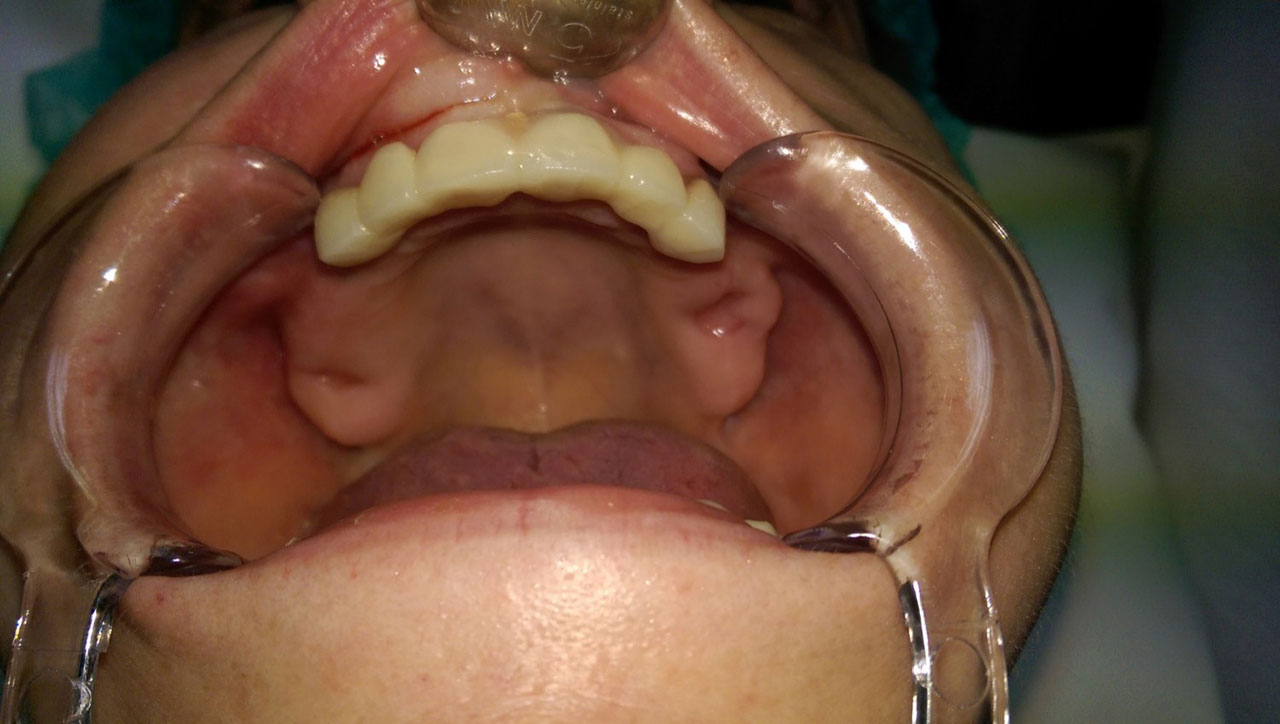

• esettanulmany-34

A felső állcsont teljes implantációs helyreállítása.

• esettanulmany-32

72 órávan a felső állcsont teljes implantációs helyreállítása után, így mosolyog a páciens a beragasztott, fix hiddal.

• esettanulmany-46

A felső állcsont teljes implantációs helyreálítása.